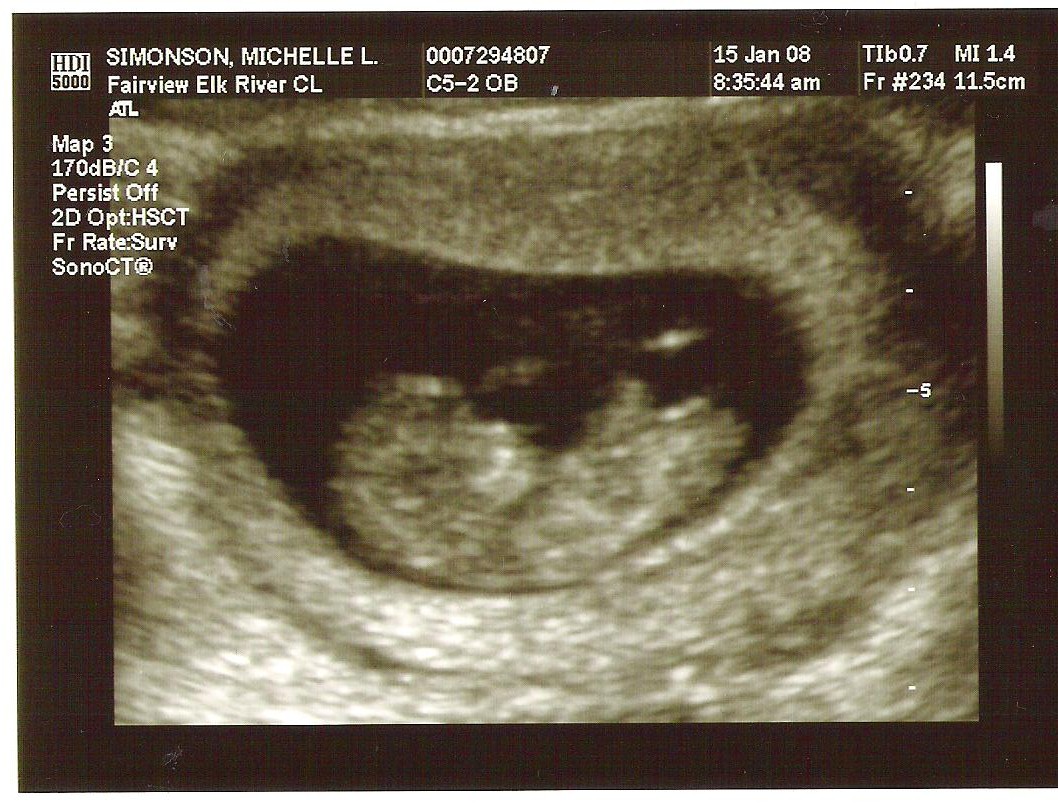

Babies First Pictures!!! ITS A BOY!

Yes we got a new dsmer coming into the world soon. We got our ultrasound today and its gonna be a boy. And shes a lot further along then we had originally thought. Shes due on April 15th which puts her at almost 6.5 months, (and really not showing it.) He weighs currently ~2lbs. He even opened his mouth while on camera which was really cool.

Here are the pics.

Pic 1: The babies head profile

Pic 2: Mouth is open!

Pic 3: NWS Baby Penis! lol

Pic 4: Long little legs!

Pic 5: Big Feet just like his mama.

Well Im jumping on the Baby bandwagon too. Just got the first Ultrasound today about 11 weeks along.